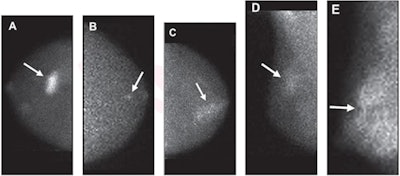

MBI uses a small-field-of-view gamma camera to image radiotracer uptake within the breast, and it is used as a supplement to screening with standard digital mammography or to guide treatment. Previous research suggests that MBI has a supplemental cancer detection rate of eight to nine cancers per 1,000 women screened when used along with digital mammography.

Breast radiologists developed a lexicon in 2012 for MBI that mirrors the lexicon used for imaging descriptors in the BI-RADS atlas. This lexicon includes descriptors for mass versus nonmass radiotracer uptake, distribution of nonmass uptake, and lesion intensity.